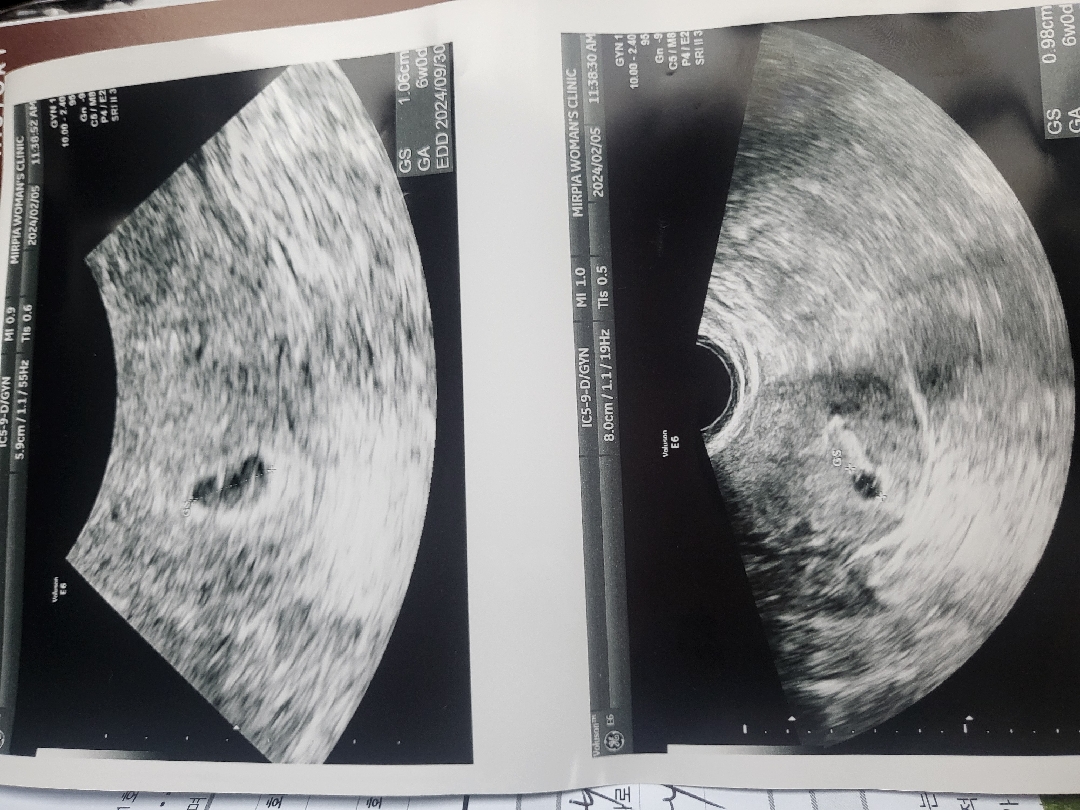

6주입니다..심장소리아직못들었고 아이가좀더컷음좋겠다는 의사쌤말..그래도 저번주보단커서다행이긴한데 담주엔괜찮겠죠?매일초음파를볼수도없공 ㅠㅠ

착상이 좀 늦어서 그럴수있어요 저도 6주에 심장소리 못들었고 1주뒤에 가서 훌쩍 커져있는 아기와 우렁찬 심장소리 듣고왔어요 너무 걱정마세요!

그렇겠죠?1년전에7주계류유산하고 1년만에다시찾아온아이라..ㅠ걱정이이만저만아니네요..